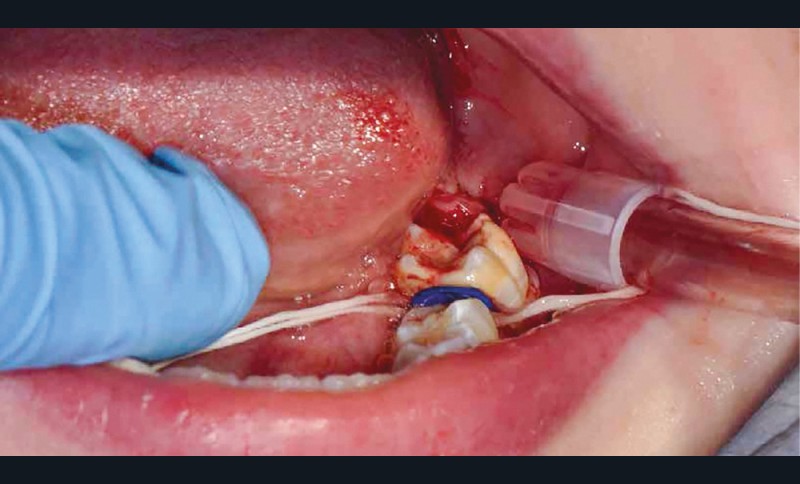

Afin d’optimiser les séances de soins, l’anesthésie intra-osseuse par injection électronique a été réalisée avec le Quicksleeper 5® dans les deux secteurs (fig. 3 et 4) afin de permettre la réalisation des coiffes préformées métalliques sur 36 et 46 dans la même séance (fig. 5 à 7). Il aurait été difficilement envisageable de réaliser les coiffes dans la même séance en utilisant une anesthésie tronculaire dans chaque secteur.